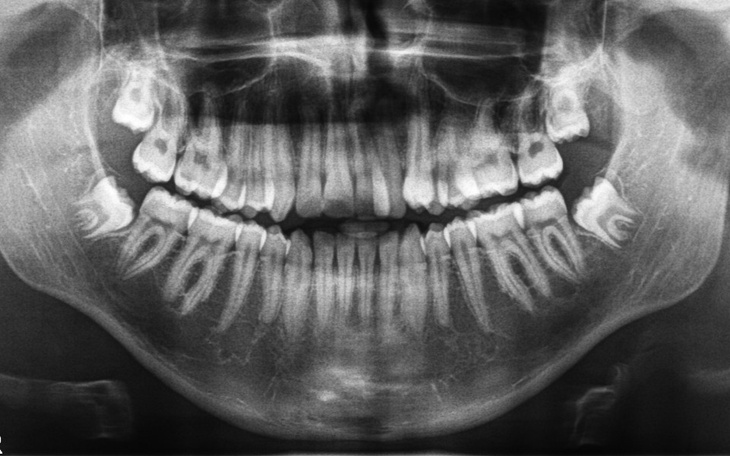

Jestem samotną matką pracujaca na etacie. Ostatnio dowiedziałam się jak poważną wadę zgryzu mają obaj moi synowie. Dzieci wymagają szybkiego leczenia ortodontycznego niestety z racji wieku nie kwalifikują się już do aparatów refundowanych. Obaj synowie z racji wieku a starszy dodatkowo z tytułu zaawansowania wady zgryzu. Zbieram tylko na aparaty koszty wizyt i dodatkowych zabiegów pokrywam z swoich środków